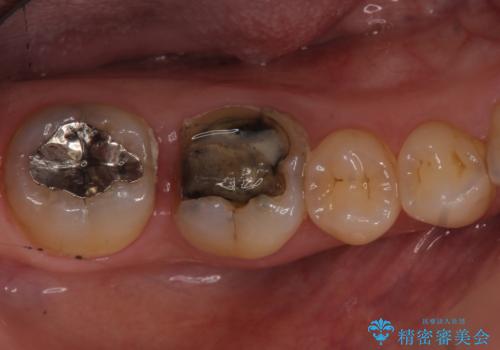

- 右下奥歯の詰め物が取れたとのことで来院されました。

セラミックでの治療をご希望されましたが、残っている歯が少なかったためクラウンでの治療を行いました。

もう一つ奥の歯に関してもセラミックにやり替えたいとのことでしたので、こちらはインレーでの治療を行いました。